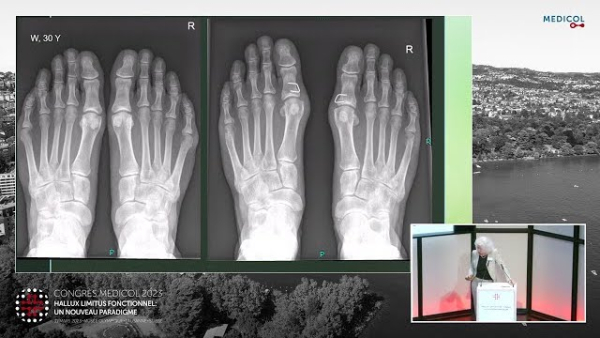

Hallux limitus fonctionnel

Imagerie

Dr Olivier Leluc - Congrès Medicol…